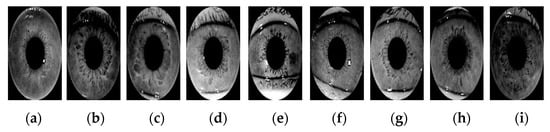

In this study, we propose a practical health assessment system that combines DL with the philosophy of TCM and iridology, which evolves into a convenient and portable tool that is able to predict possible organ dysfunction and give advice to subjects about how to take care of their health according to the body constitution assessment. According to the advice of iridology experts from TIII, the key to body constitution using iridology lies in the third zone (ring) of the iris chart. We summarized the classification rules and present them in the form of a table. Table 4 shows the classification of five elements based on the third zone (ring) of the iris chart. Figure 4 shows 15 examples of iris images corresponding to five TCM elements, based on the classification criterion in Table 4. Figure 5 shows the samples of iris images of the derived nine categories (with primary and secondary type), which were used in our experiments.

Figure 5. Samples of iris images of the derived nine categories (with primary and secondary type). (a) Fire and wood; (b) Earth and Metal; (c) Earth and Water; (d) Earth and Wood; (e) Fire and Metal; (f) Fire and Water; (g) Metal and Water; (h) Water and Wood; (i) Wood and Metal.